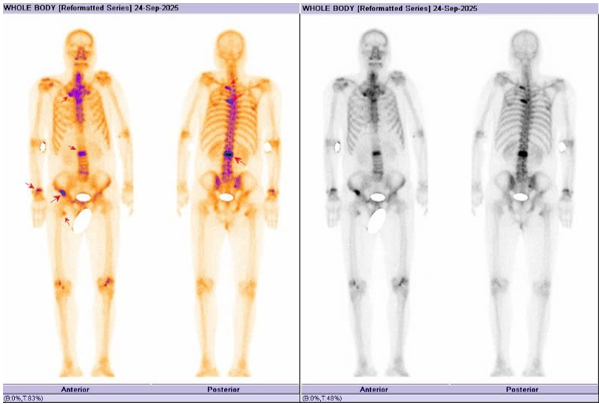

Hình 4: Hình ảnh xạ hình xương cho thấy các ổ tăng hoạt độ phóng xạ nhiều vị trí tại xương cột sống, xương đòn phải, xương chậu phải, cung sau xương sườn 2, 5 bên trái, đầu dưới xương cẳng tay bên phải, đầu trên xương đùi phải hướng đến tổn thương thứ phát.